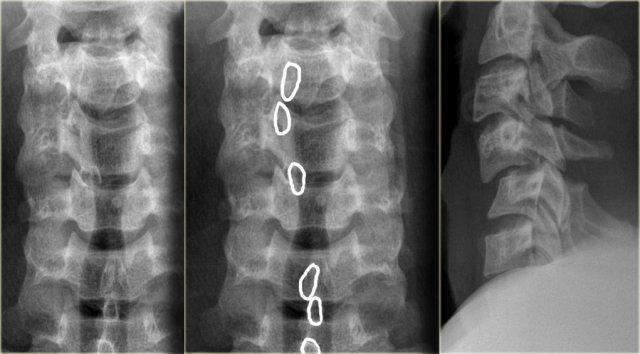

Hình bên trái là một trường hợp gãy mỏm răng loại II khác.

Đôi khi các đường gãy này có thể khó nhận thấy.

Có những hình ảnh giả gãy xương như các đường thấu quang do chồng hình (overprojection) hoặc đường Mach nổi bật (hình minh họa).